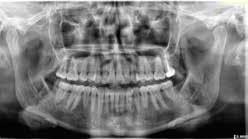

A maradó fogak gyökérreszorpciója patológiás folyamat. Az elváltozások elhelyezkedése alapján csoportosíthatjuk őket külső és belső reszorpciós folyamatokra. A külső gyökérreszorpciók egyre gyakrabban diagnosztizált formája a külső nyaki reszorpció (angolul External Cervical Resorption, ECR) [1. és 2. kép]. Az ECR egy komplex elváltozás, amely egyszerre érintheti a fog keményszöveti állományát, a parodontális szöveteket és előrehaladott esetben a pulpaszövetet is. A modern diagnosztikai eszközöknek köszönhetően egyre gyakrabban és egyre korábban kerül diagnosztizálásra ez a típusú lézió, így a kezelése is egyre inkább a mindennapi klinikum részévé válik az endodonciával foglalkozó kollégák számára. A 3 dimenziós diagnosztikai eszközök terjedésével felmerült az igény egy 3 dimenziós klasszifikációra. Patel és munkatársai 2018-ban kidolgoztak egy új klasszifikációt, amely segít az elváltozások kategorizálásában és a kezelések tervezésében [1]. A téma aktualitását jól mutatja, hogy ezzel egy időben az ESE (European Society of Endodontology) is kidolgozott egy állásfoglalást a külső nyaki reszorpciók diagnosztikájával és terápiás lehetőségeivel kapcsolatban [2].

Ötvenes éveiben járó hölgyet fogorvosa irányította hozzánk a bal alsó 4-es fogának nagy méretű reszorpciójával [9. kép]. A hölgy ragaszkodott foga megmentéséhez, így a kezelés megtervezéséhez CBCT felvételt készítettünk a fogról [10. kép]. A felvételen a Patel-féle klasszifikáció szerinti Patel 3Ap reszorpciós elváltozás látható. A szájüregi vizsgálat során a fog bukkális felszínén gyulladt ínyt, mély parodontális tasakot és a fog nyaki részén, a foganyagon átsejlő reszorpciós lacunát találtunk [11. kép]. A fog szenzibilitás vizsgálat során nem reagált hideg ingerlésre. A pulpális érintettség miatt elvégeztük a fog trepanálását, majd lebenyt alakítottunk a kavitás láthatóvá tételéhez [12. kép]

1. és 2. kép: Külső nyaki reszorpciós elváltozások CBCT képen.Kónuszos felépítmény kapcsolat